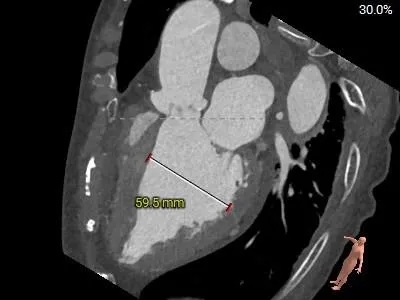

术前CT分析

主动脉根部测量

Annulus

24.5mm

LVOT

30.8mm

水平夹角

39°

SOV

32.1*29.9*31.6mm

STJ:27.7mm

高度19mm

AAO

33.5mm

左心室测量

左心室腔内径偏大,心室壁厚度尚可

入路情况

双侧外周血管内径可,走形适宜,右侧股动脉分叉偏高